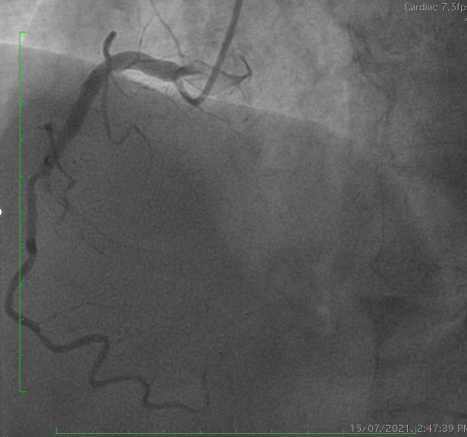

Coronary angiography demonstrated a patent LAD stent and CTO in-stent restenosis (ISR) at mid RCA with ipsilateral collateral flow from the RV branch to the PDA. Anatomical challenges included a proximal RV branch near the CTO cap, a nearly 90¡Æ CTO entry angle, a lesion length of ~60 mm, and distal bifurcation involvement. The CTO had a tapered stump with a visible microchannel. The J-CTO score was 2.

PCI was performed via single radial access with a 6F short-tip AL guiding catheter and Finecross microcatheter. 3D wiring with UB3 under orthogonal views; escalation to Gaia 3. Anchor ballooning in the RV branch improved support. The wire successfully crossed into the PLV. Predilation with a small balloon, followed by scoring ballooning. A Crusade dual-lumen catheter enabled Gaia 3 wiring into the PDA, which was predilated with a 2.5 mm balloon. IVUS revealed undersized and extensively malapposed stents contributing to ISR and prior very late thrombosis. High-pressure NC 3.75 mm ballooning improved expansion, though full correction was limited by the original stent size. A hybrid treatment strategy was chosen—DCB for both PLV and PDA (3.0¡¿20 mm and 3.0¡¿15 mm respectively, with DCB-assisted kissing), and DES reconstruction of the mid-to-proximal RCA using 4.0¡¿38 mm and 4.0¡¿20 mm stents delivered with guide extension support. Final IVUS confirmed optimal expansion and apposition without edge dissection. Final angiography showed TIMI 3 flow with no complications. At 9 months, angiography demonstrated patent RCA stents and positive remodeling at the PLV ostium.